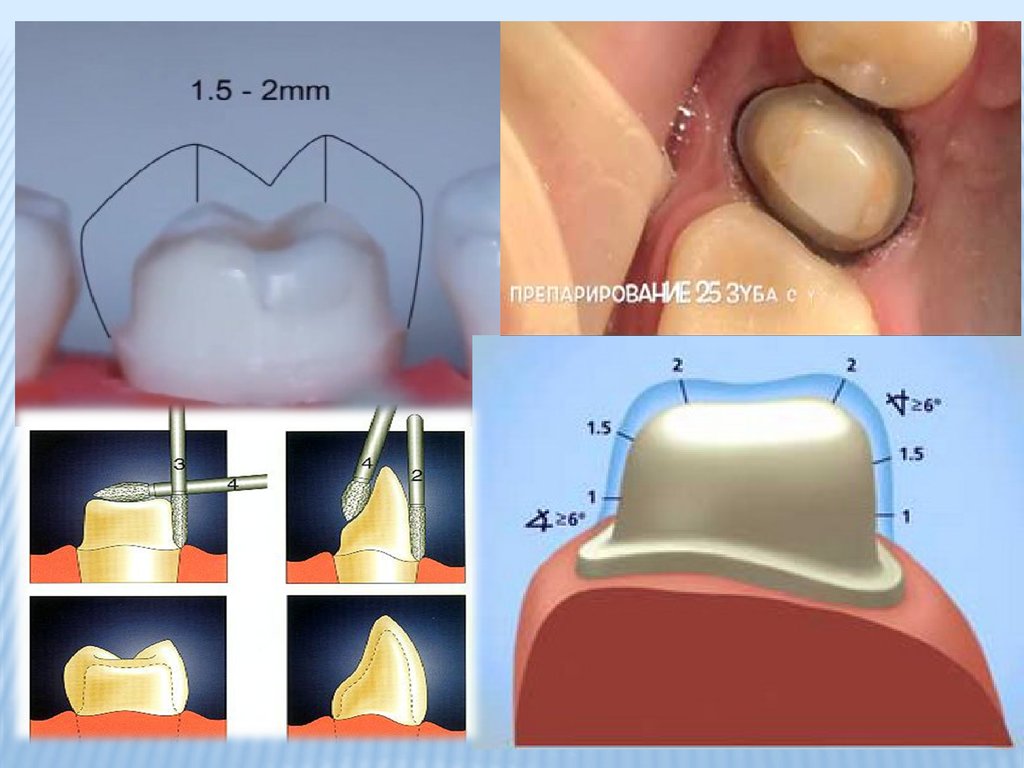

Культя зуба это

Культя зуба это 106 фото